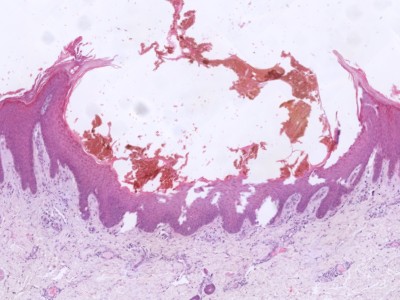

PA:Afwijkende clusters van

misvormde venule-achtige vaten

in de diepe dermis en subcutis, in combinatie met reactieve epidermale acanthose,

papillomatose, en hyperkeratose. Positief voor GLUT-1 (glucose transporter type-1)

en WT1 (Wilms tumor-1). GLUT-1 wordt vaak gezien in vasculaire tumoren.

![Histologie verruceus hemangioom (click on photo to enlarge) [source: Kevin Kwee / Afdeling Pathologie MUMC] Histologie verruceus hemangioom](../../../pacoupes/thumbnails/verruceus-hemangioom-1.jpg) |

![Histologie verruceus hemangioom (click on photo to enlarge) [source: Kevin Kwee / Afdeling Pathologie MUMC] Histologie verruceus hemangioom](../../../pacoupes/thumbnails/verruceus-hemangioom-2.jpg) |

ingescande coupe (zoom) |

Bron

hoge resolutie PA-foto's: Kevin Kwee en Afdeling Pathologie MUMC. Klik

op de afbeelding om in te zoomen.